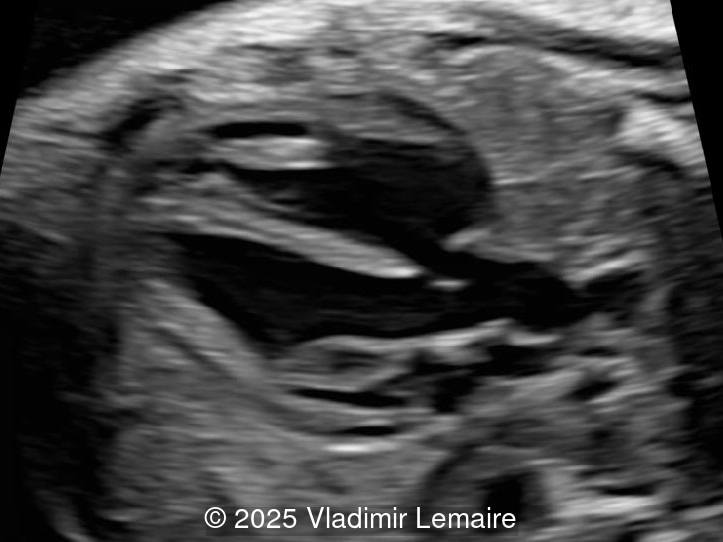

A 39-year-old patient, G1P0, presented to our maternal fetal medicine unit at 30 weeks of gestation for a growth scan. The fetus was male with low-risk noninvasive prenatal testing. The following findings were observed.

• Image 1: Transverse view of the upper abdomen at the level of the abdominal circumference.

• Image 2: Axial plane of the fetal chest at the level of the four-chamber view. Note the normal appearance of the four-chamber view.

• Images 3 and 4: The five-chamber view shows the ventricular septal defect and the dilated overriding aorta.

• Image 5: The right ventricular outflow tract view with color Doppler demonstrates a small main pulmonary artery when compared to the dilated aorta due to pulmonary stenosis.

• Image 6: The three-vessel-trachea view with color Doppler shows the discrepant size of the great arteries with the pulmonary artery smaller than the aorta. Note the presence of antegrade blood flow in both arteries.

In the images below, the following abbreviations are used: RV (right ventricle); LV (left ventricle); Ao (Aorta), VSD (ventricular septal defect), Ao V (Aortic valve); PA (pulmonary artery)